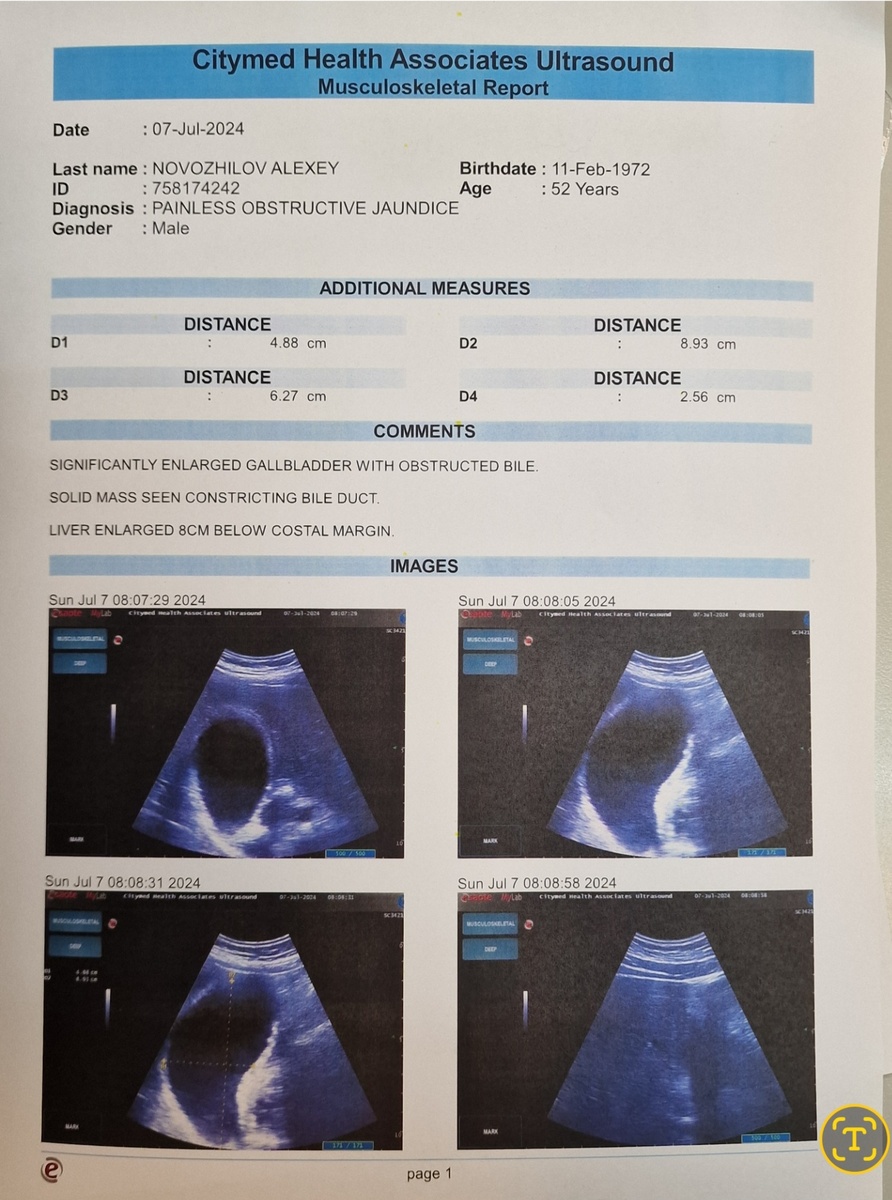

Сделал УЗИ, развернул монитор ко мне и выдал: "Братан! У тебя опухоль поджелудочной железы! Ты никуда не плывёшь, не летишь, а едешь в наш SGH (Singapore General Hospital).

С вот этим я заехал в госпиталь.